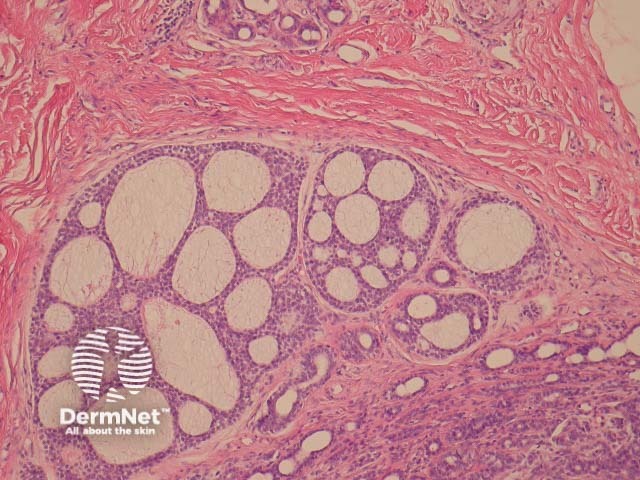

Polymorphous sweat gland carcinomas are dermally based tumours (figure 1) that show a wide range of morphologic growth patterns ranging from solid, tubular (figures 2, 3), cribriform (figure 4) and ductal. Abrupt transitions between morphologies is a characteristic feature (figure 5, 6).

Figure 4